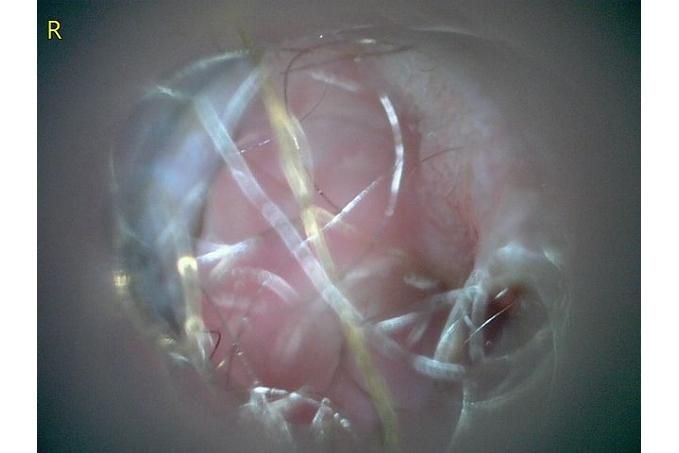

사진만 보고 확진할 수는 없지만 지금 올려주신 귀는 적어도 오른쪽은 정상으로 보이기 어렵습니다 왼쪽은 비교적 연분홍에 가까워 보이지만 오른쪽은 털과 분비물이 많이 차 있고 피부가 자극받은 듯한 모습이라 외이염 가능성을 먼저 생각하게 됩니다 그리고 질문자님이 적어주신 머리 털기 하루 여러 번 귀 만질 때 통증 솜만 닿아도 예민함 귀 긁기 같은 증상은 외이염에서 흔한 신호입니다

지금 제일 조심해야 할 것은 귀세정을 무조건 하는 것도 무조건 안 하는 것도 아니라는 점입니다 고막 상태를 확실히 모르는 귀에 자극적인 세정제를 넣거나 세게 세정하면 더 아프고 더 깊은 쪽을 자극할 수 있습니다 특히 알코올 성분 세정제는 염증 있는 귀에서 따갑고 자극적일 수 있고 고막이 손상돼 있으면 더 문제가 될 수 있습니다 그래서 지금처럼 오른쪽이 아픈 귀는 집에서 강하게 세정하는 쪽은 저는 말리고 싶습니다

귀약도 사진만으로 어떤 약이 맞다고 정해드리기는 어렵습니다 외이염 치료는 보이는 모양만이 아니라 현미경 검사에서 세균인지 효모인지 귀진드기인지에 따라 달라지고 실제 수의학 자료도 이경 검사와 세포검사를 바탕으로 약을 고르라고 설명합니다 다만 통증과 부종이 심한 외이염에서는 스테로이드가 들어간 점이약이 부기와 통증을 줄이는 데 도움이 되기도 합니다 쿠싱이 있어도 바르는 약이 전신 먹는 약보다 몸 전체 영향은 적은 편이지만 아예 영향이 없다고는 못 하므로 정말 필요한지와 기간을 짧게 쓸지까지 같이 따져야 합니다